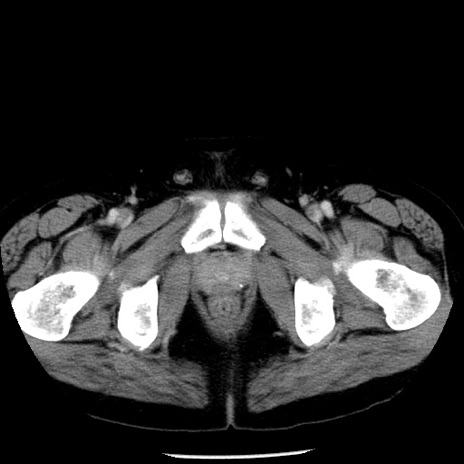

症例29(横断像)

【症例】40歳代男性

【現病歴】2日前から胃痛あり。徐々に周期的な激痛に変化した。本日になっても激痛があるため受診。

【身体所見】意識清明、BT 38-39℃台あり、腹部:膨満、やや硬、右下腹部に圧痛あり。

【データ】WBC 8500、CRP 23.26